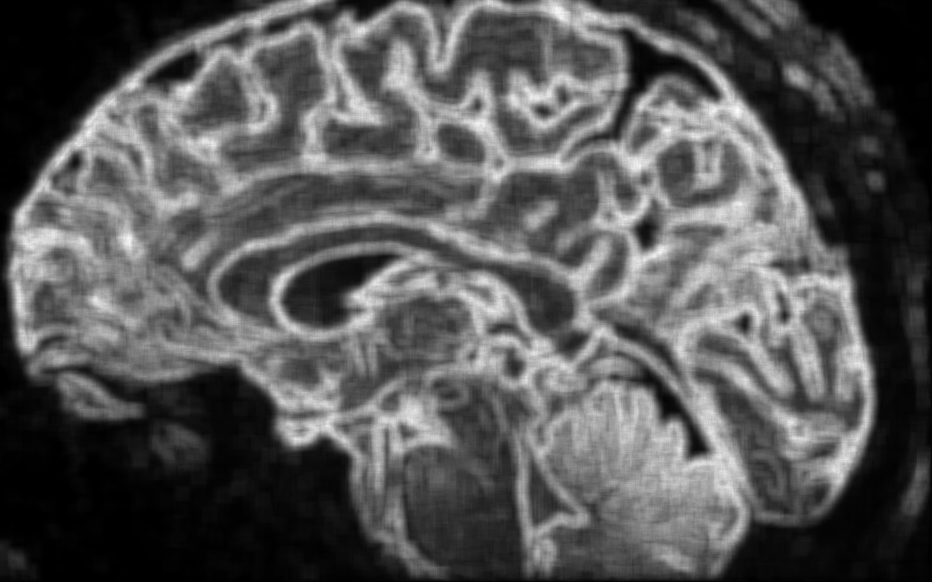

Voir n’est plus regarder : c’est comprendre la structure du monde cellulaire.

Loin du contraste classique, ϕ explore la richesse interne des tissus.

Elle distingue l’homogène du structuré, le bruit du sens, et redonne au regard médical une dimension topologique : celle de l’information vivante.

Les structures fines, souvent invisibles à l’œil nu, s’y dessinent comme des reliefs entropiques — un paysage du corps, révélé par la mathématique du vivant.